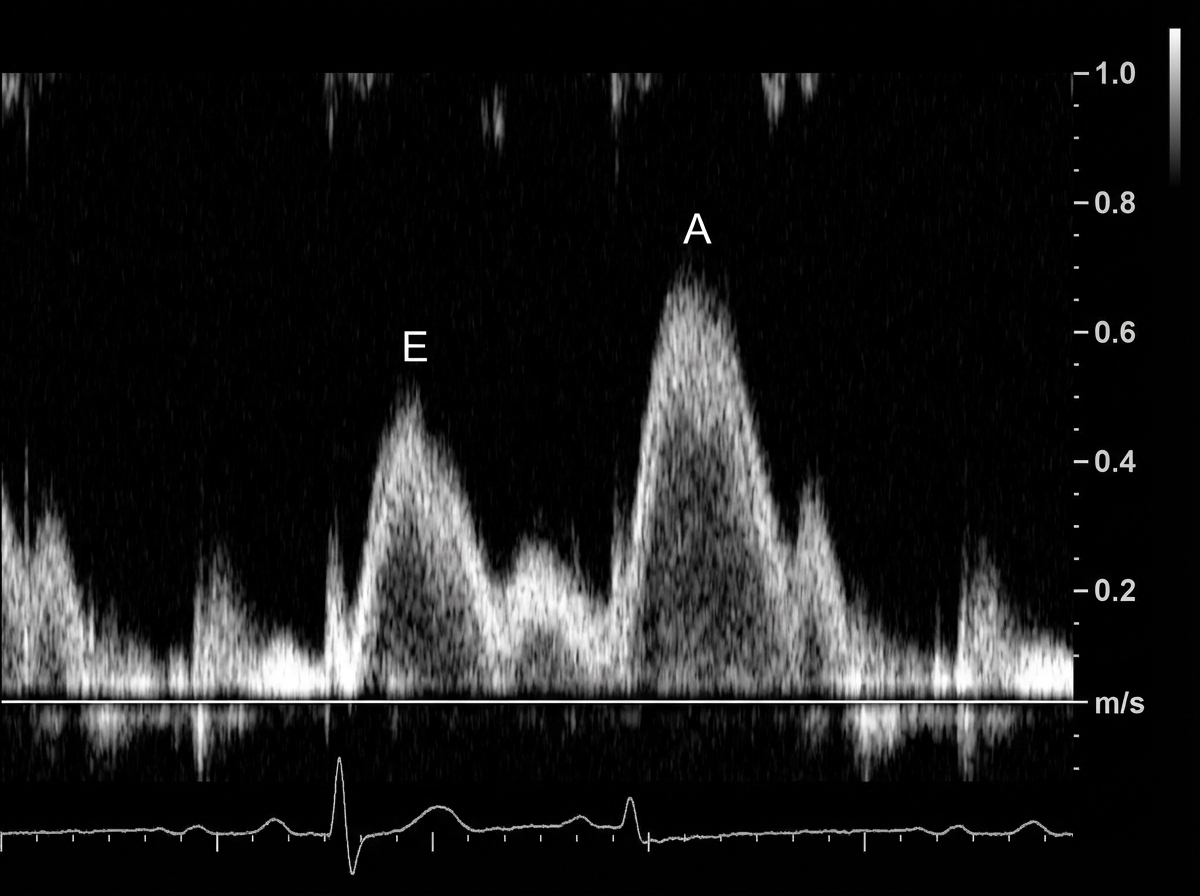

- Pathophysiology (Diastolic Dysfunction): Impaired ventricular relaxation and filling leads to ↑ left ventricular end-diastolic pressure (LVEDP). The ventricle can't relax, so it can't properly fill.

- Auscultation Hallmark: An S4 gallop is often heard, representing atrial contraction into a stiff, noncompliant ventricle.

⭐ Despite significant heart failure symptoms, the ejection fraction remains normal or near-normal (EF ≥ 50%), as the systolic 'squeeze' function is preserved.